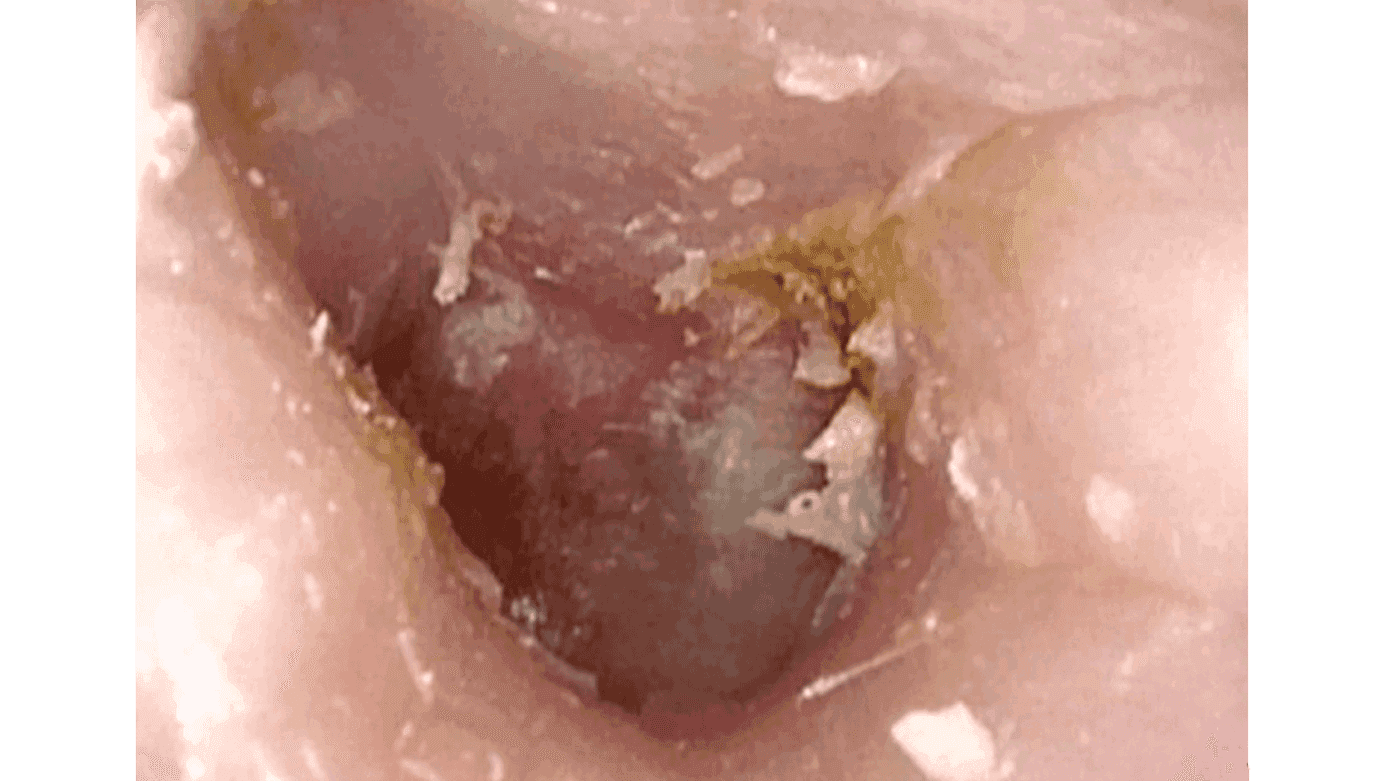

Øre-næse-hals artikler fra Ugeskrift for Læger 20/2025StatusartikelBenigne spytkirteltumorer13. okt. 202512 min.KasuistikIdiopatisk bilateral vestibulopati13. okt. 20255 min.Ugens billedeUspecifikke halssmerter7. jul. 20252 min.KasuistikEksostose ved den indre øregang2. jun. 20254 min.KasuistikKraftig blødning efter biopsi fra nasofaryngealt juvenilt angiofibrom14. jul. 20255 min.StatusartikelNye behandlingsmuligheder for kronisk hoste6. okt. 202513 min.